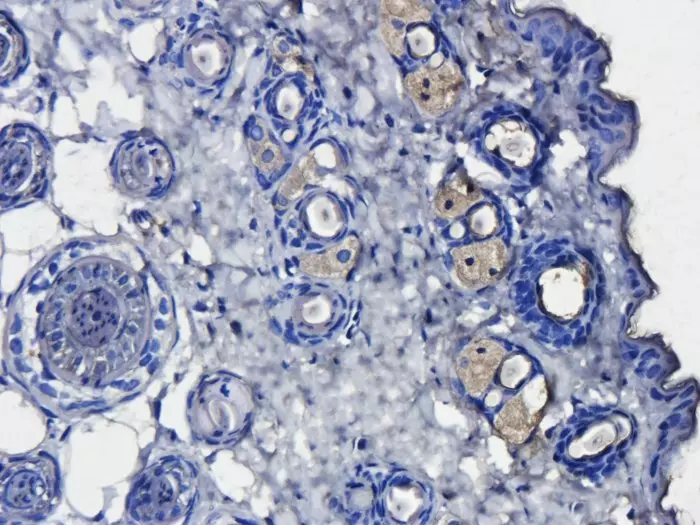

Immunohistochemistry (IHC) is an invaluable tool for researchers in clinical settings and laboratories. A combination of IHC techniques results in clear imaging of specific tissue components. Labeled antibodies are used to bind to specific target antigens in situ and combined with optimized staining, cells and components are visualised with clarity. IHC can provide accurate data revealing distribution, quantity and intensity of expression to enhance and validate your research. Your protocol design will affect your results, the choices within the protocol will impact the quality of the results you achieve. Use Biorbyt’s experience, along with our vast range of high quality products, to support your research at every stage.

IHC is used by researchers globally to diagnose disease, in drug development and in a wide range of biological research. Identification of cells, components, their origins and pathology can be visualised in glorious colour using IHC in isolation or combined with other techniques. Cellular activity in response to specific chemicals can be observed and quantified to understand efficacy during drug development. Modern IHC techniques allow high-throughput, multiparametric, accurate data analysis at all levels of research.

Use a chromogenic substrate or fluorescent dye to detect signal viewed using light or fluorescence microscopy.